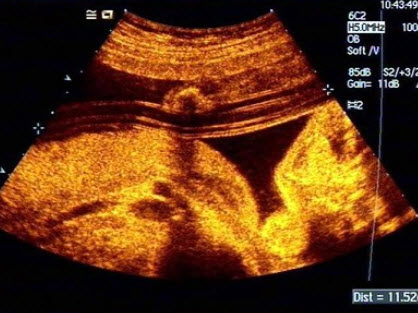

13、单项选择题

如图,最可能的诊断是()

A.软骨成长不全

B.致死性骨发育不全

C.窒息性胸廓发育不良

D.肢体屈曲综合征

E.无肢畸形